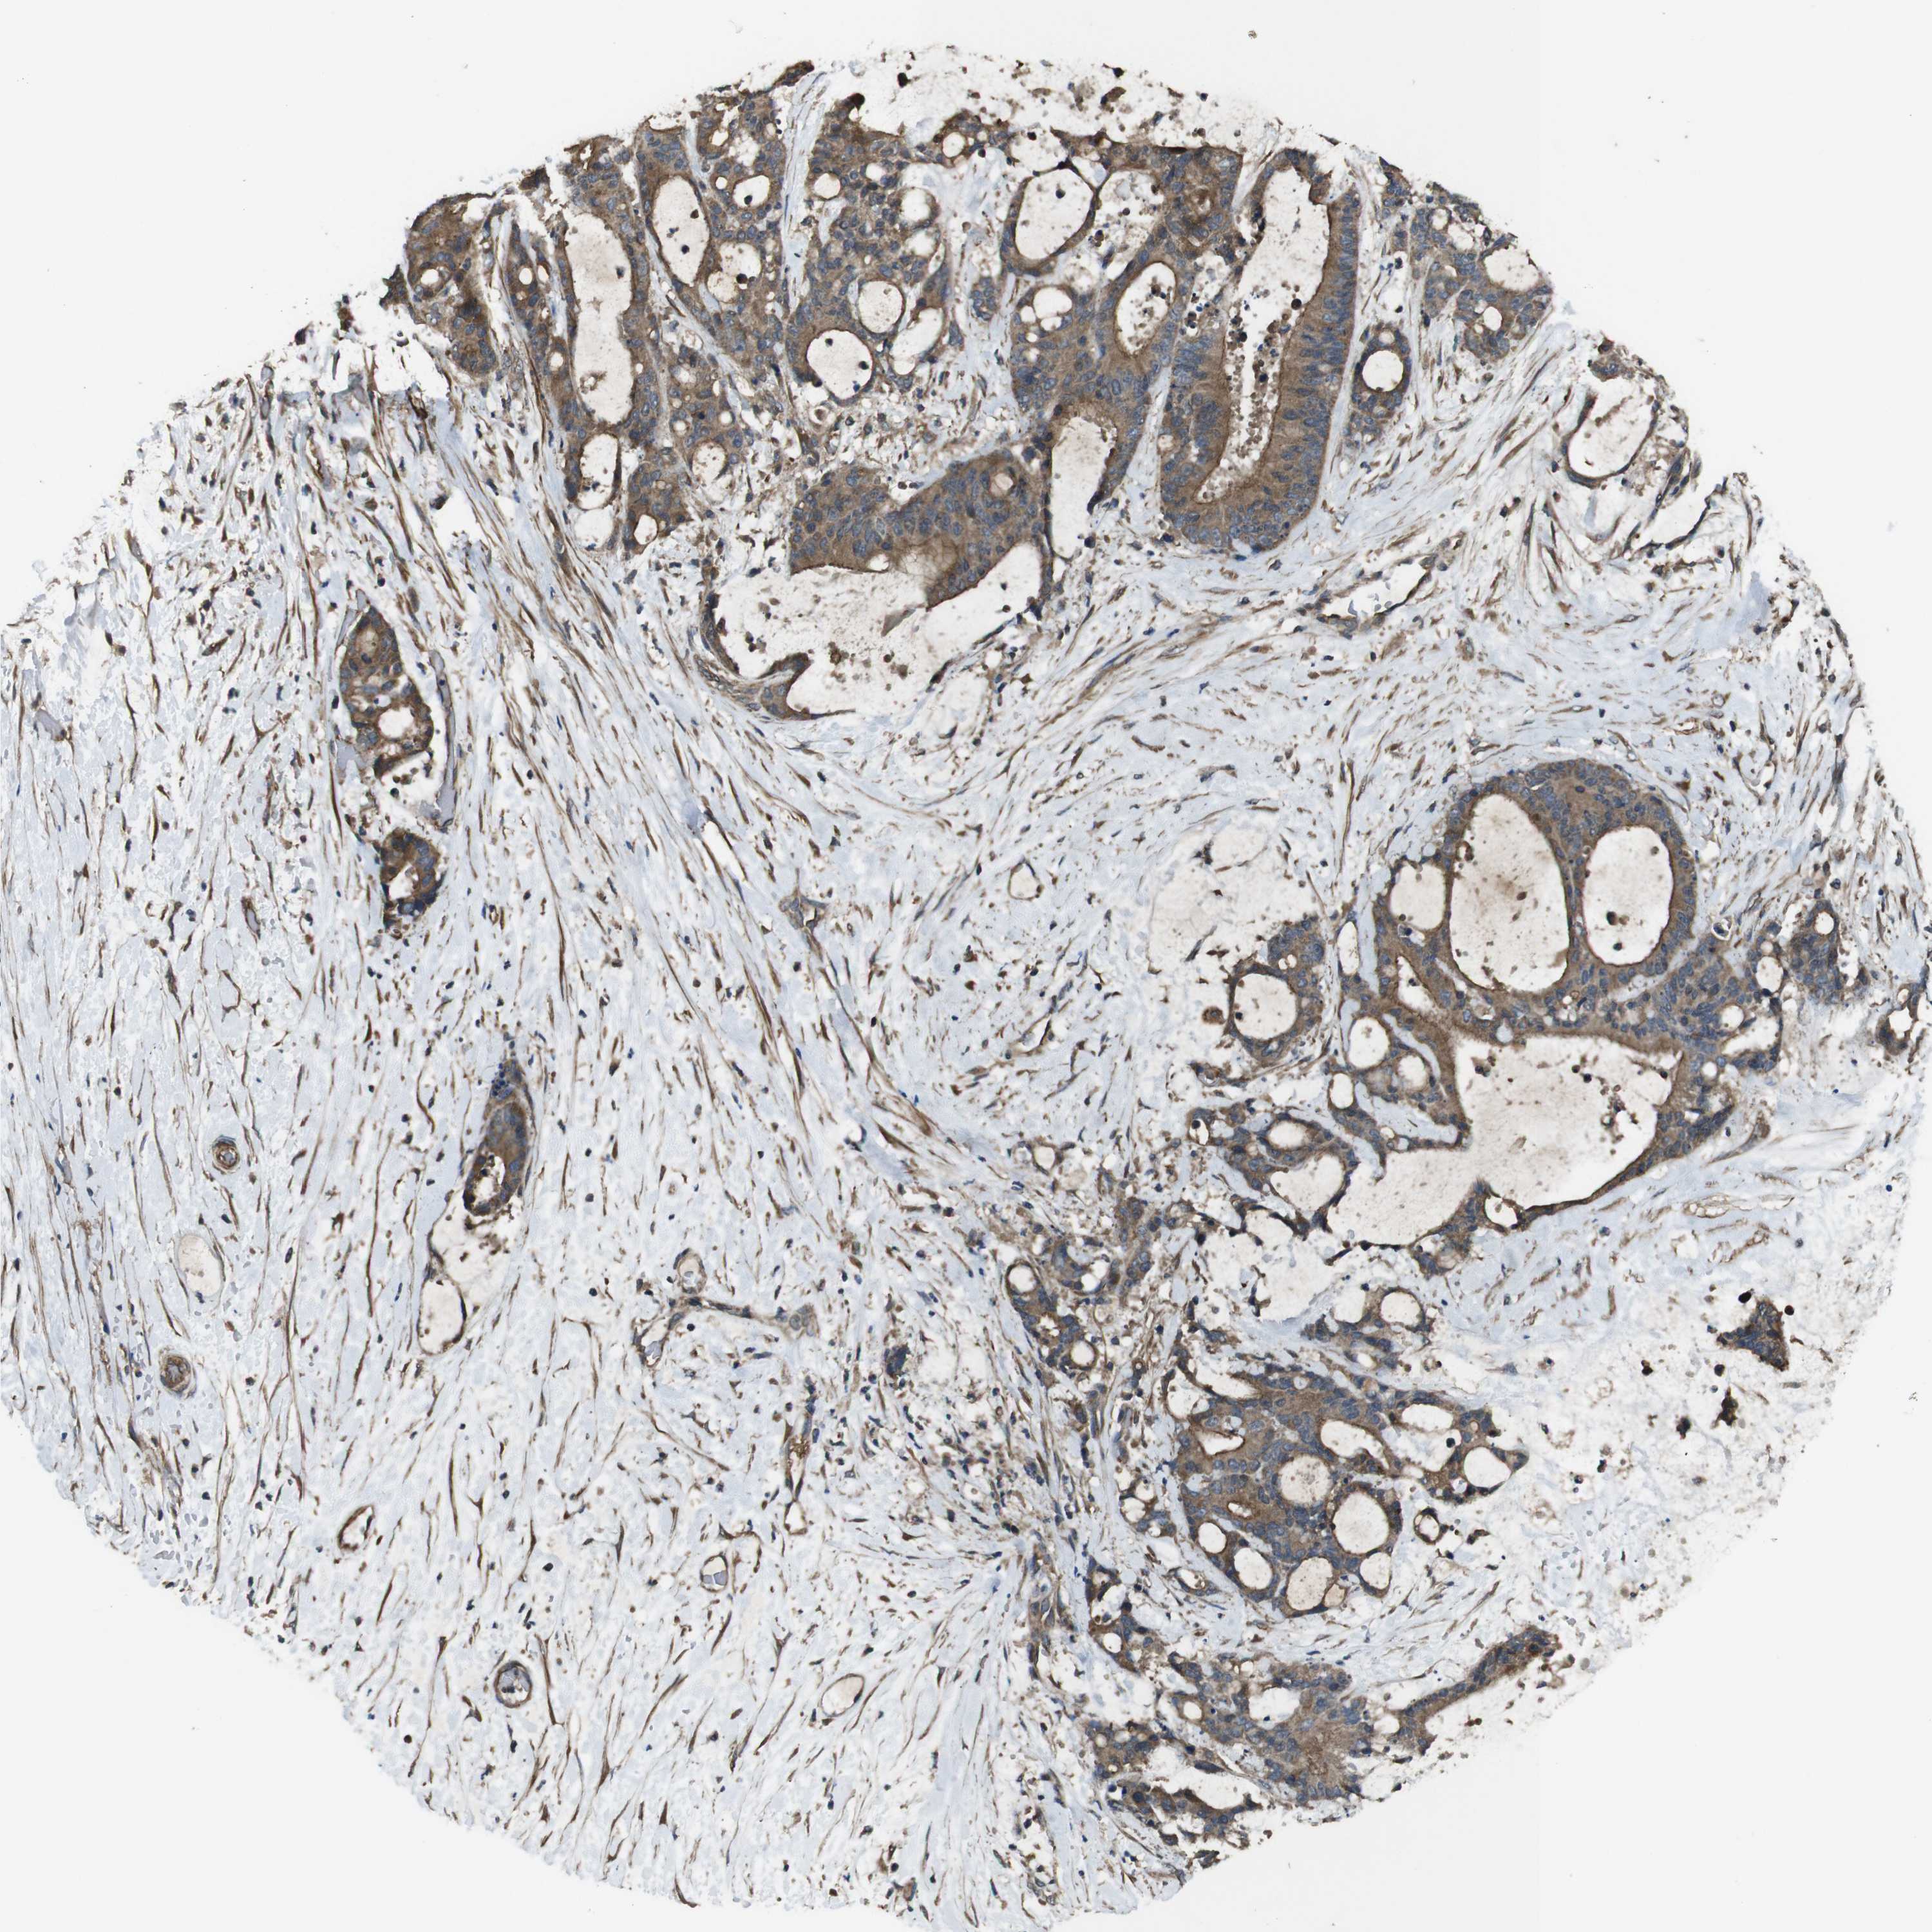

LIVER CANCER - Protein expressioni

A mouse-over function shows sample information and annotation data. Click on an image to view it in a full screen mode. Samples can be filtered based on level of antibody staining by selecting one or several of the following categories: high, medium, low and not detected. The assay and annotation is described here.

Note that samples used for immunohistochemistry by the Human Protein Atlas do not correspond to samples in the TCGA dataset.

Antibody stainingi

Antibody staining in the annotated cell types in the current human tissue is reported as not detected, low, medium, or high, based on conventional immunohistochemistry profiling in selected tissues. This score is based on the combination of the staining intensity and fraction of stained cells.

Each image is clickable and will lead to virtual microscopy that enables deeper exploration of all samples and also displays staining intensity scores, fraction scores and subcellular localization as well as patient and tissue information for each sample.

Antibody HPA014402

Staining

High

Medium

Low

Not detected

Intensity

Strong

Moderate

Weak

Negative

Quantity

>75%

75%-25%

<25%

None

Location

Nuclear

Cytoplasmic/membranous

Cytoplasmic/membranous,nuclear

Cholangiocarcinoma

Carcinoma, Hepatocellular, NOS